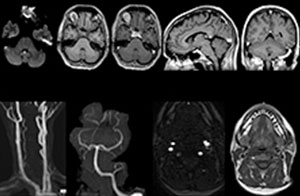

“We use mDIXON TSE extensively in our spine imaging in the emergency room,” says Dr. Karis. “It’s particularly nice in that it is very robust with regard to susceptibility type of problems that would come up with traditional spectral fat-saturated images; these problems are essentially eliminated with the mDIXON technique. In our ED environment it’s really nice to have the fat-free imaging that goes along with the mDIXON technique.

“For the thoracic and cervical spine routine non-contrast exam, for example, we perform one mDIXON T2 TSE sequence, which provides us with two outputs: the fat-and-water-together T2-weighted images, as well as the water-only sagittal T2-weighted images. And then we also perform an axial gradient echo exam.”